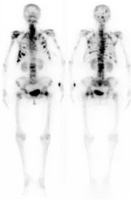

全身多发骨转移